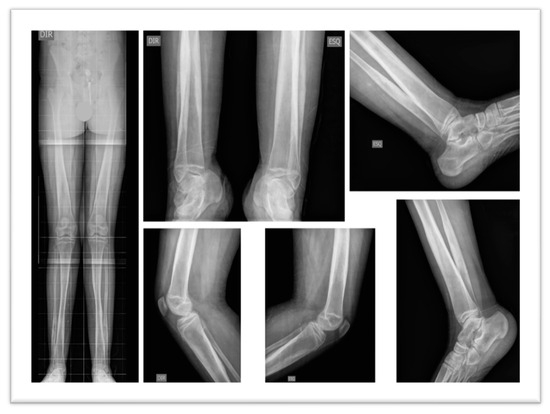

In 2024, blood and urine tests were conducted, including fasting glucose, urea, creatinine, uric acid, lipid profile, Aspartate Aminotransferase (AST), Alanine Aminotransferase (ALT), Creatine Kinase (CPK), potassium, sodium, glycated hemoglobin, Thyroid-Stimulating Hormone (TSH), Free Thyroxine (T4), Triiodothyronine (T3), vitamin B12, vitamin D, and folic acid, all within normal reference values. Hemogram results showed slightly low hemoglobin levels, 13.5 g/dL (reference: 14.0 to 18.0 g/dL) and lymphocytosis, 6400/µL (reference: 800 to 4000/µL). Urinalysis revealed dark yellow, slightly turbid urine, with a pH of 5.5, density of 1.028, traces of hemoglobin, hematuria (12,100/mL), presence of calcium oxalate crystals and mucus filaments. Thoracic radiographs were normal; pelvic radiographs showed morpho structural changes in both hips characterized by verticalization and flattening of the acetabula, as well as cortical thickening of the femoral diaphysis bilaterally and apparent hypotrophy of the quadriceps muscles (Figure 2A). Additionally, spinal radiographs described a slight deviation of the thoracolumbar spine to the right, with no vertebral rotation (Figure 2B).

Figure 2. Radiographic Images. (A) Pelvis: Morpho structural changes in both hips characterized by verticalization and flattening of the acetabula, as well as cortical thickening of the femoral diaphysis bilaterally and apparent hypotrophy of the quadriceps muscles. (B) Spine: Slight deviation of the thoracolumbar spine to the right, with no vertebral rotation.